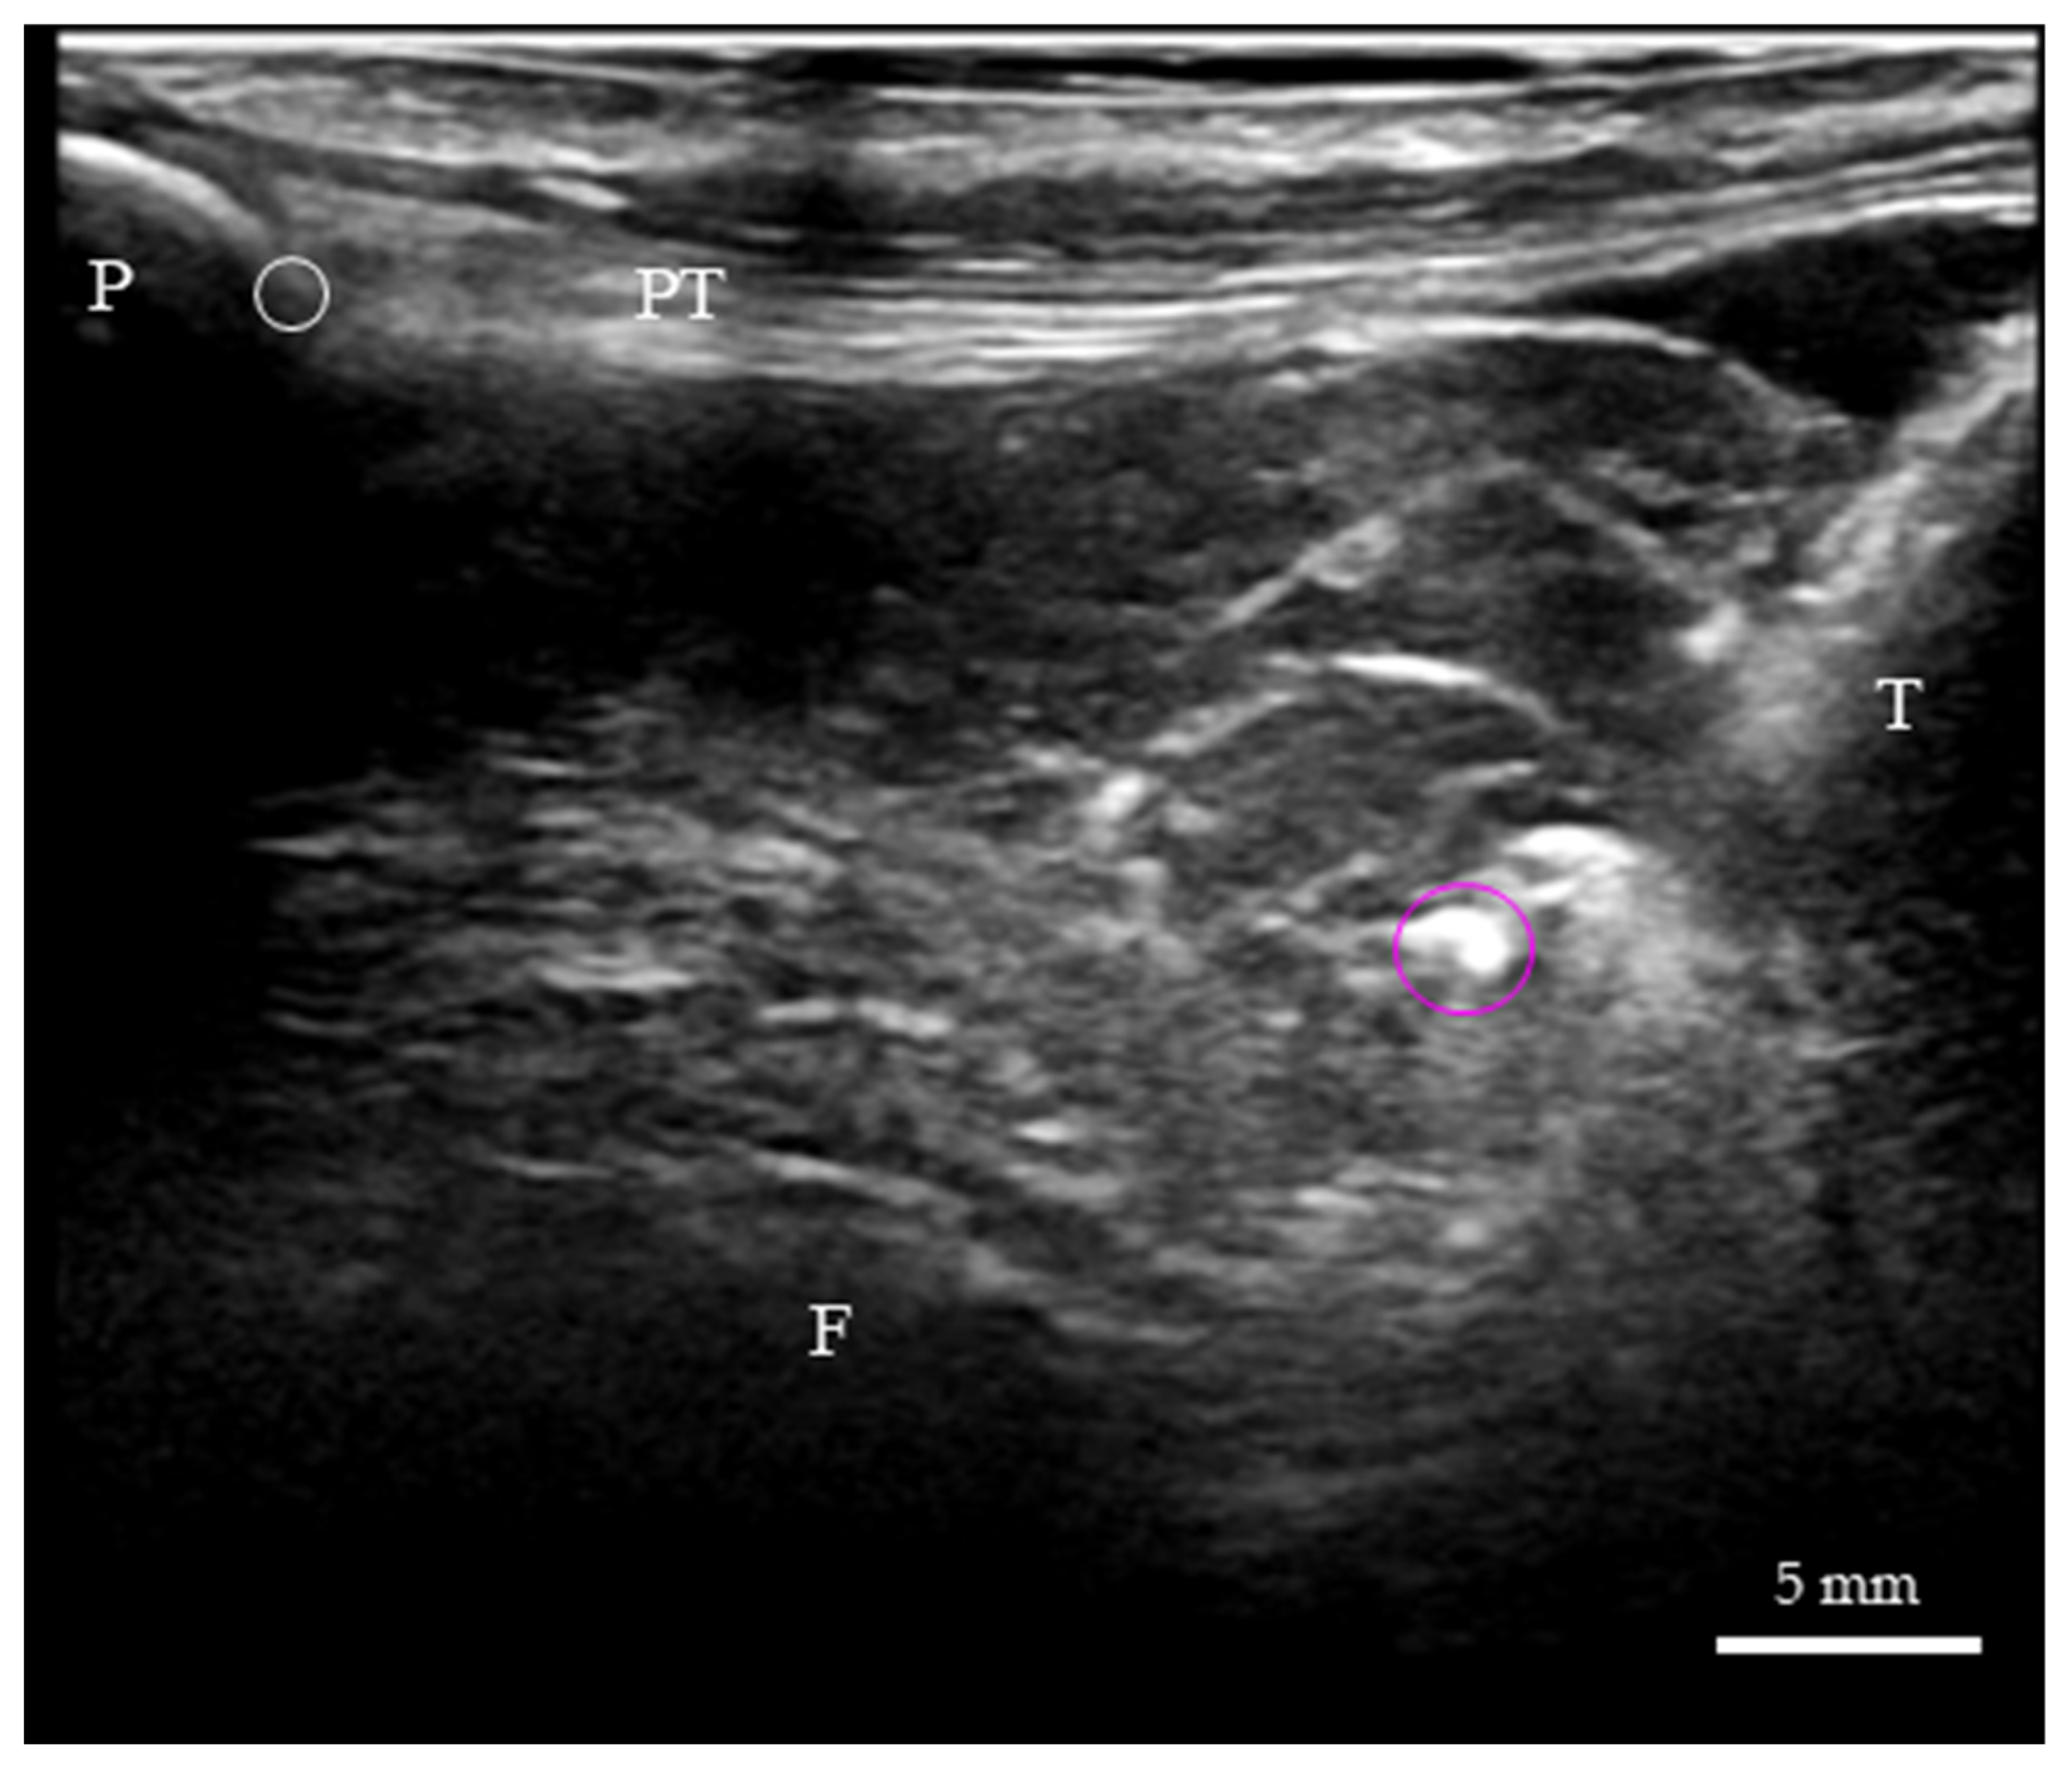

| AFC-SEG [Target Region] | Adipo-Follicular Segment | Bounded by SPD-SEG, IPP-SEG, and tibia. Connected to the anterior horns of the menisci. | Contains unique follicle-like spaces. Highly compliant and susceptible to joint pressure changes. |